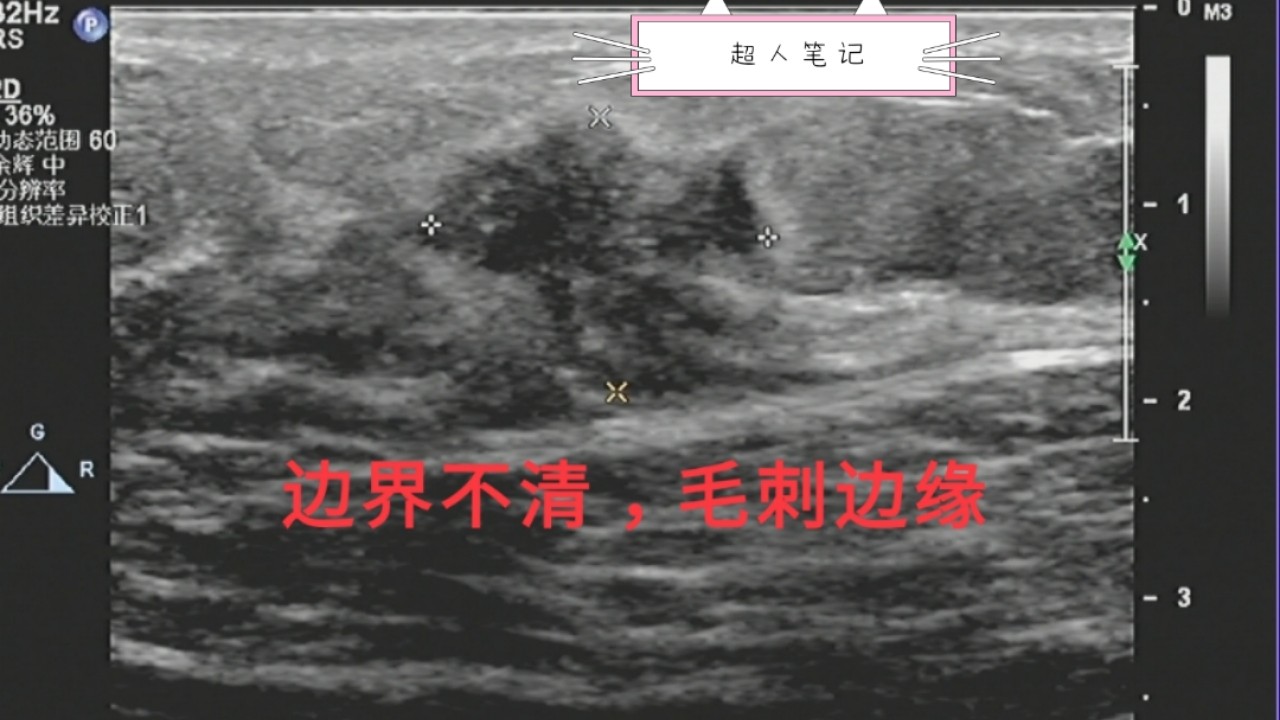

2、肿块不规则,会有分叶情况,典型的有“蟹足状”。

3、边界不清,毛刺状边缘。